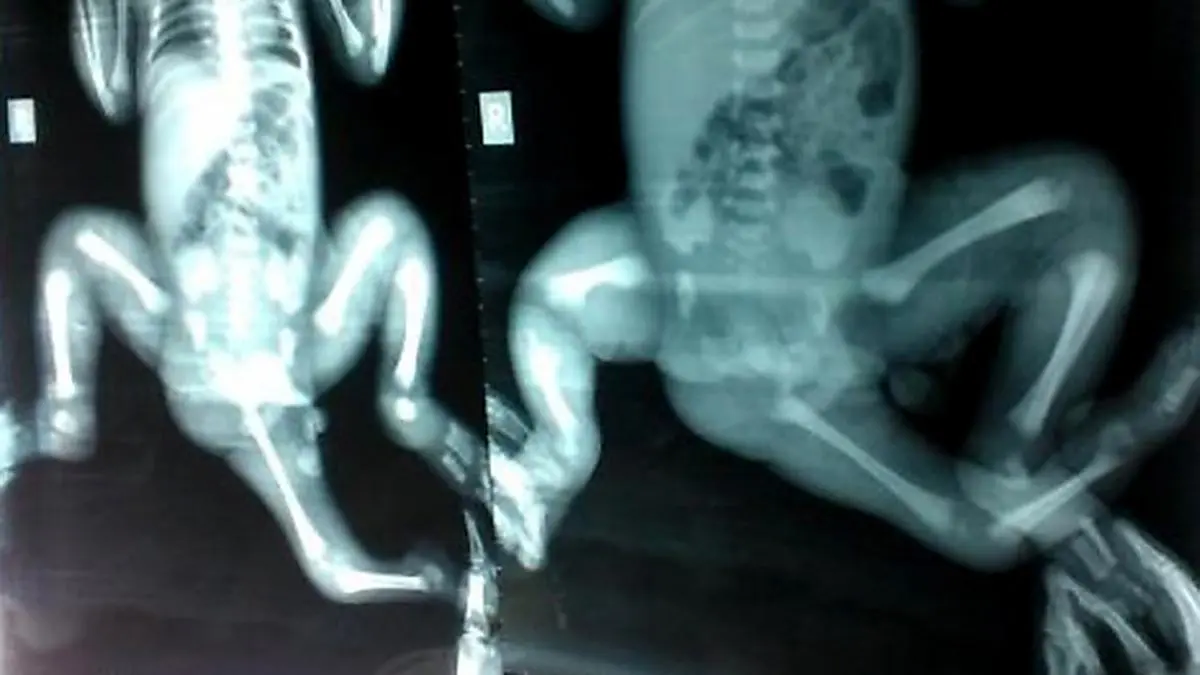

Mädchen mit drei Beinen in Australien operiert

In einer aufwendigen Operation hat ein australisches Ärzteteam einem mit drei Beinen geborenen kleinen Mädchen aus Bangladesch ein Bein entfernt und den Unterleib rekonstruiert, so dass es endlich laufen und rennen kann. Die dreijährige Choity Khatun war "sehr unterernährt, sie konnte überhaupt nicht richtig gehen", als sie im vergangenen Jahr nach Australien kam, sagte ihr Arzt Chris Kimber.